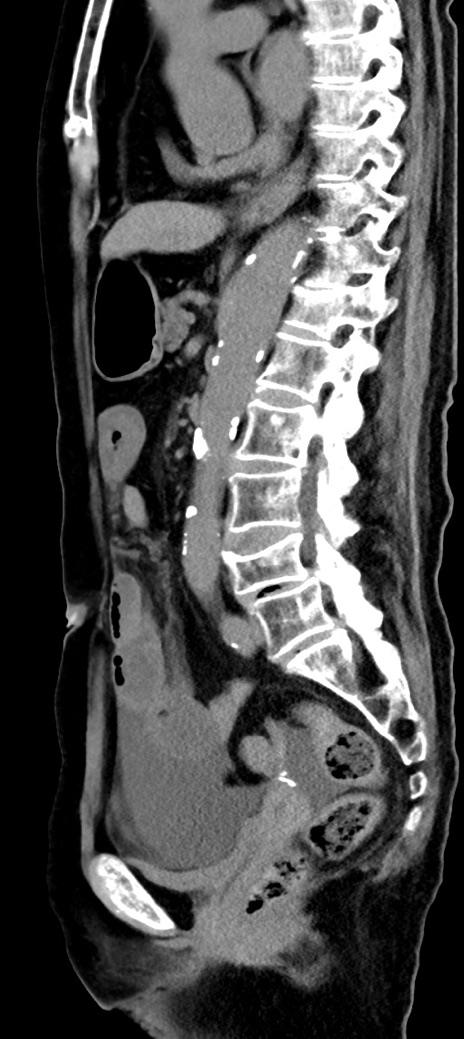

症例40(矢状断像)他院1日前

【症例】90歳代女性

【主訴】腹痛・嘔吐

【現病歴】 食欲低下、嘔吐があり昨日他院受診。肺炎と診断され入院となる。入院後より腹部全体に圧痛あり。胃管留置され経過みていたが、症状持続するため、

当院転院となる。

【既往歴】胸椎圧迫骨折、胆石症

【身体所見】腹部:中央に激痛あり、圧痛あり、反跳痛不明

【データ】WBC 17100、CRP 18.82